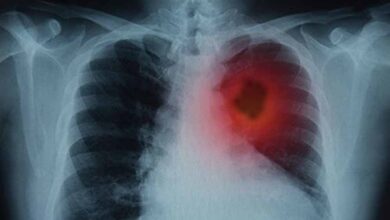

कैंसर उपचार में क्रांतिकारी खोज: वैज्ञानिकों ने फेफड़ों के ट्यूमर घटाने का नया तरीका विकसित किया

फेफड़ों के कैंसर से जूझ रहे लाखों लोगों के लिए विज्ञान की दुनिया से एक बहुत बड़ी और राहत भरी…

भारत में कैंसर की बढ़ती चुनौती: पुरुषों में फेफड़े और महिलाओं में ब्रेस्ट कैंसर सबसे आम

नई दिल्ली आईसीएमआर-नेशनल सेंटर फॉर डिसीज इंफॉर्मेटिक्स एंड रिसर्च (NCDIR) के एक अध्ययन से पता चलता है कि भारत में…